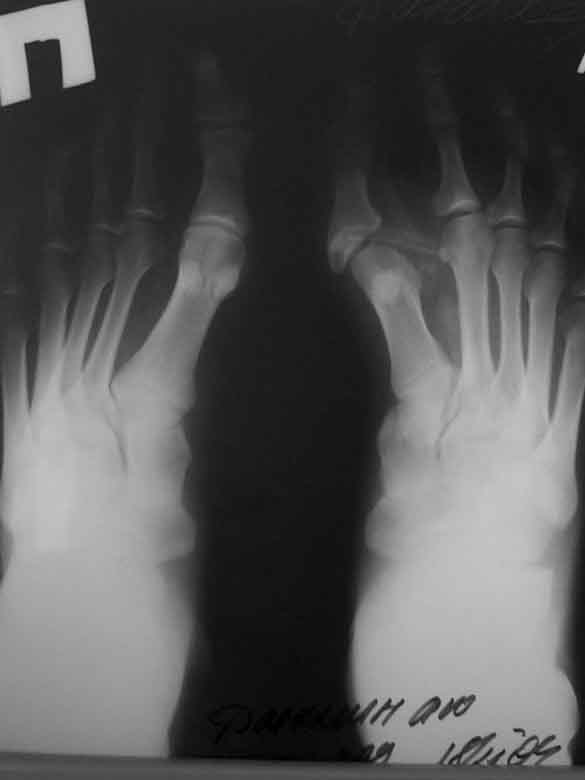

Прилагаю послеоперационные рентгенограммы.

Планирнуем использовать приводящуюю шину для 1 п.

Вопрос о проведении реконстрнуктивных операций на костях поднимем при наличии жалоб.